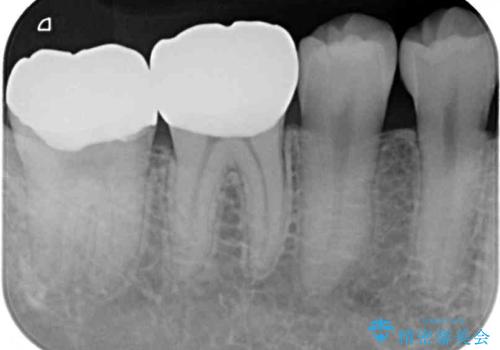

- 右下奥歯の虫歯がしみて痛いとのことで来院された患者様です。

神経近くにまで及ぶ大きな虫歯でしたが、速やかに処置を行い、痛みは即日解消されました。

虫歯が大きかったため、クラウンによる補綴治療が必要になる旨をお伝えしたところ、矯正治療にも興味があるとのことでした。

短期間で手間のかからない方法がご希望でしたので、ワイヤー装置による矯正治療を行うこととし、矯正治療後に右奥2歯をセラミッククラウンにて補綴することとしました。